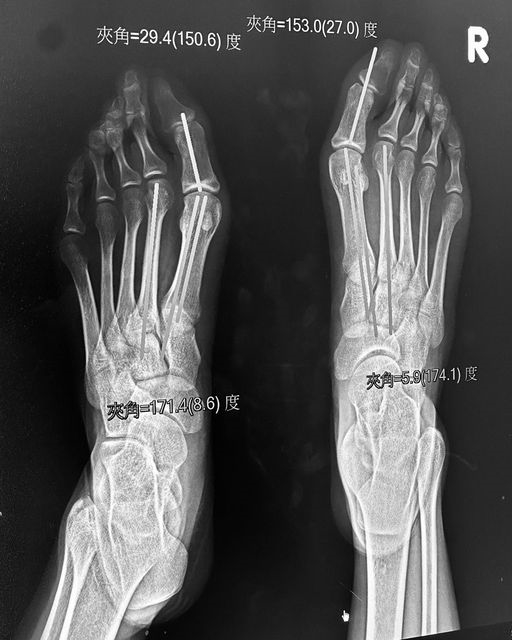

邵雨薇昨(31)日在臉書上傳一張雙腳X光照,只見她雙腳的大拇指明顯歪斜,她也無奈表示「Happy halloween,拇指外翻了啦」。文章曝光後,引來不少粉絲擔憂,「保重呀!」、「多穿寬鬆舒適透氣的鞋子!高跟鞋少穿!長期把腳都擠壓變形了」、「怎麼會這樣」、「辛苦的藝人!穿休閒舒服的鞋!別虐待自己!」,也有網友歪樓,笑說這是「透視女明星內在」。